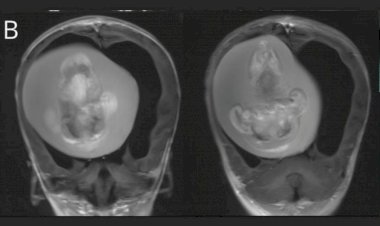

Menina passa por cirurgia para retirar feto de irmão gêmeo...

O feto de 10 centímetros foi descoberto após a criança passar por exames de imagem...